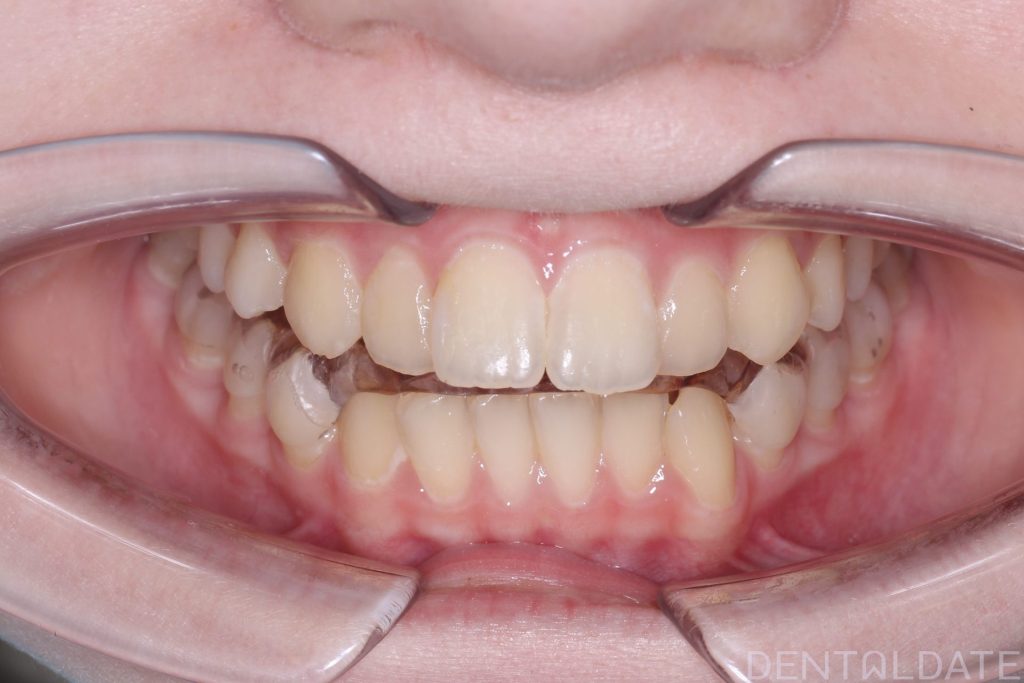

After a follow-up MRI confirmed the correct jaw position, braces were installed.